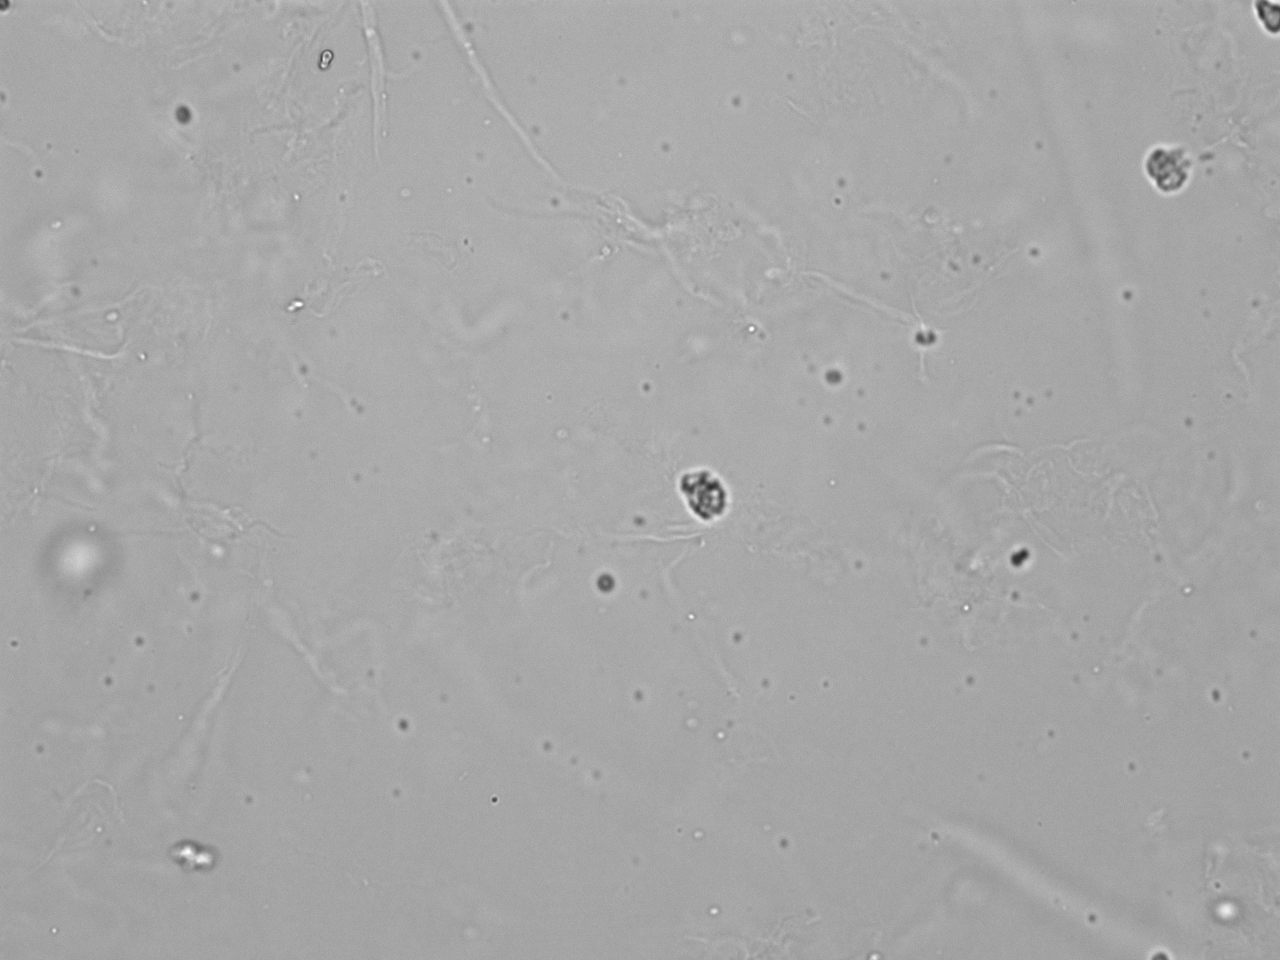

Probe mit leichter Leukozyturie und Mikrohämaturie; Bildmaterial für Explorer-Demo.

Mikroskopie-Bilder